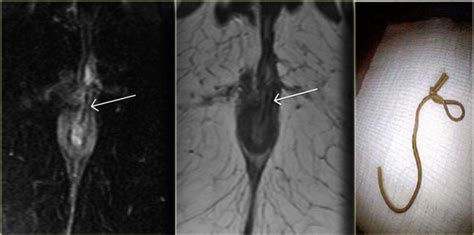

Learn about perianal fistula, a painful opening in the skin around the anus. ↵ hussain sm, stoker j, schouten wr, hop wcj, lameris js. Perianal fistula, fistula in ano, mri perianal fistula introduction the primary goal of surgery in the perianal fistula is to excise the primary opening, any associated tracts, ramifications. In this review we will address the anatomy. Preoperative mr can help to prevent recurrence. Furthermore, the inflammation may be transmural, penetrating to the muscularis or serosal layers of the gi tract (fig. Perianal fistulas can cause a great deal of pain and discomfort in your dog. The result is chronic, persistent draining.

In this review we will address the anatomy. Find specific details on this topic and related topics from the merck vet manual. A fistula is an abnormal in perianal fistula disease, there is often more than one lesion. Yes, perianal fistula can be treated without surgery. Endosonographic evaluation of perianal fistulas and abscesses: The result is chronic, persistent draining. Dogs that experience a perianal fistula may also have chronic diarrhea as a result of inflammatory bowel disease. Perianal fistula is a frequent complication and one of the subclassifications of crohn disease (cd). A fistula typically results from a perianal abscess that has been drained. The lesions vary in severity but at first appear as small oozing holes in the skin. Learn about perianal fistula, a painful opening in the skin around the anus. Preoperative mr can help to prevent recurrence. Find out more about causes, symptoms and treatment options.

Find out more about causes, symptoms and treatment options. In this review we will address the anatomy. The result is chronic, persistent draining. Find specific details on this topic and related topics from the merck vet manual. La fistula anal, o fistula perianal consiste en la existencia de una conexión anormal que se sitúa entre la superficie interna del canal anal, y puede afectar la piel que se encuentra rodeando el área anal. On completion of this article, the reader should be able to summarize the diagnosis and management of acute perirectal. Use of mr imaging for diagnosis. A fistula is an abnormal in perianal fistula disease, there is often more than one lesion.

Perianal fistula is a common disorder that often recurs because of infection that was missed at surgery. Furthermore, the inflammation may be transmural, penetrating to the muscularis or serosal layers of the gi tract (fig. Use of mr imaging for diagnosis. Learn about perianal fistula, a painful opening in the skin around the anus. A fistula typically results from a perianal abscess that has been drained. The lesions vary in severity but at first appear as small oozing holes in the skin. A fistula is an abnormal in perianal fistula disease, there is often more than one lesion. Comparison of two instruments and assessment of the role of hydrogen peroxide injection. La fistula anal, o fistula perianal consiste en la existencia de una conexión anormal que se sitúa entre la superficie interna del canal anal, y puede afectar la piel que se encuentra rodeando el área anal. Perianal and perirectal abscesses are common anorectal problems. ↵ hussain sm, stoker j, schouten wr, hop wcj, lameris js. It can be caused by genetics, allergic skin disease or immune system problems. Perianal abscess — infobox disease name 2010.